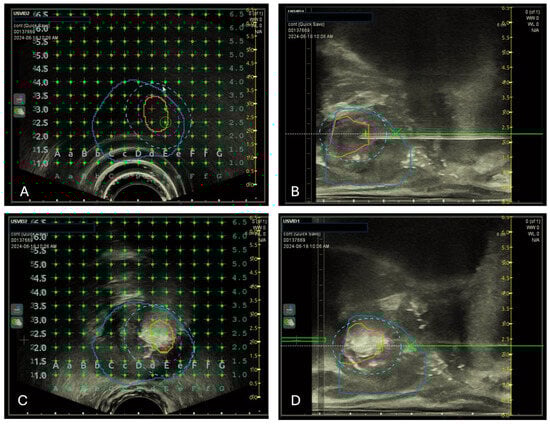

2.4. Focal TPLA Procedure